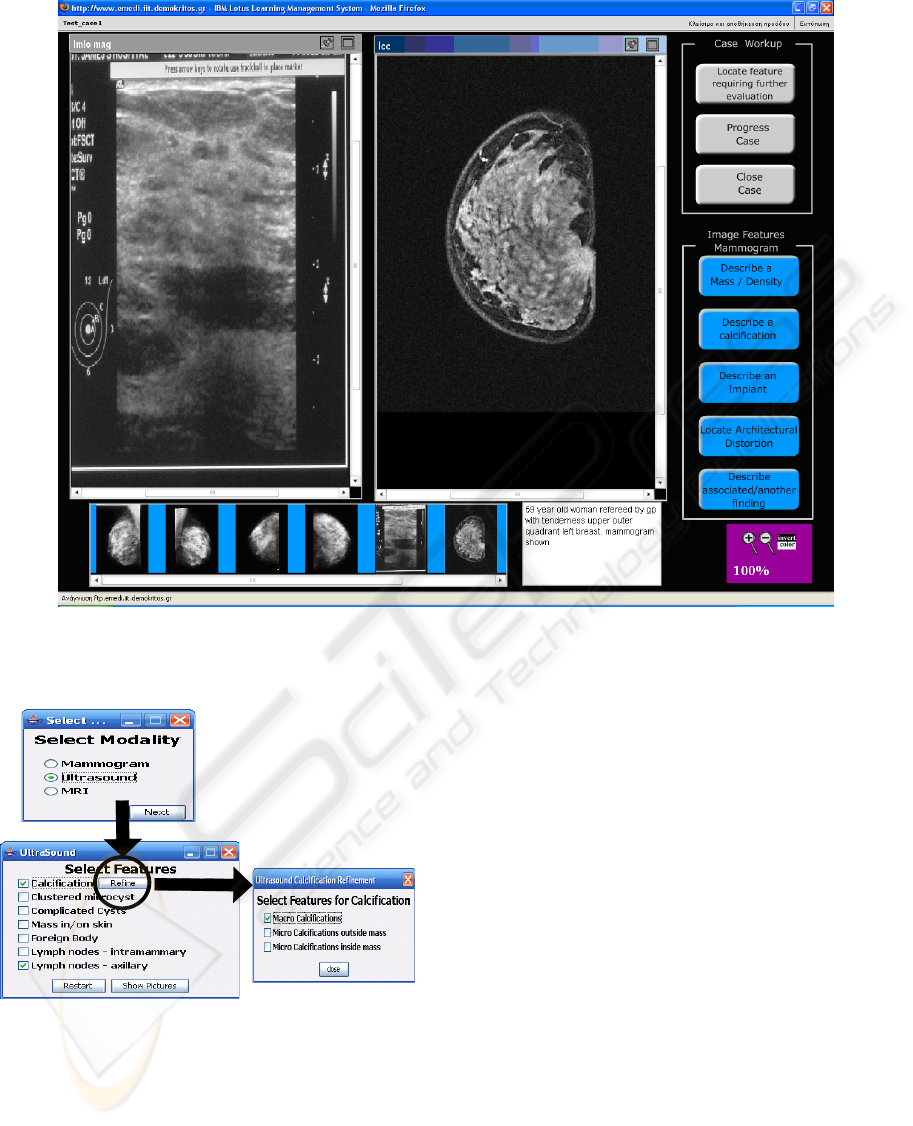

In this work, the focus is on breast imaging, but

advantages and pitfalls. Section 3 is dedicated to the

overall system architecture wherein a detailed

description of the major components will be given.